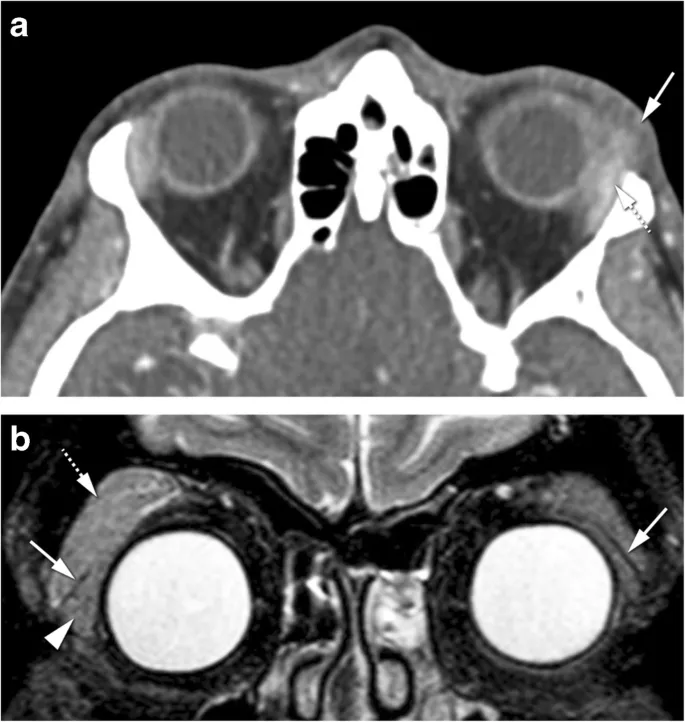

Orbital tumors demonstrate age-specific patterns with benign lesions predominating in children (85%) while malignant tumors increase with age (60% in adults >50 years). Understanding these epidemiologic patterns enables rapid differential diagnosis and appropriate treatment selection.

| Capillary Hemangioma | 0-2 years | Lid/superficial | Observation/steroids | 100% (benign) |

| Cavernous Hemangioma | 30-50 years | Intraconal | Complete excision | 100% (benign) |

The treatment algorithm depends on tumor biology rather than size alone. Slow-growing benign tumors may be observed even when large, while rapidly growing malignancies require immediate intervention regardless of size. Growth rate >2mm/month indicates malignancy in 85% of cases.

💡 Master This: Orbital metastases present with enophthalmos in 60% of scirrhous tumors (breast, gastric) due to tissue contraction, while expansile metastases (lung, kidney) cause proptosis. Bilateral orbital involvement indicates systemic disease with median survival <12 months.